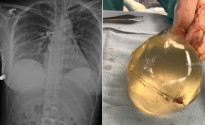

51 настай Брайн Зембик гэгч эр 17 жилийн турш хиймэл хөхтэй амьдарч байгаа ажээ. Тэрээр мэргэжлийн мөрийтэй тоглоомчин бөгөөд 1996 онд покер тоглож байгаад нэгэн эртэй мөрийцаж ийнхүү хиймэл хөхтэй амьдрах болжээ.

Тодруулбал, мөнөөх эр Брайныг бүтэн жилийн турш хиймэл хөхтэй явбал 100 мянган ам.доллар өгнө, цаашид ч хөхтэйгээ явах юм бол жил бүр үндсэн мөнгөн дээр 10 мянган доллар нэмж авахаар тохиролцсон байна.

Ингээд Брайнхэлсэн амандаа хүрэхээр шийдэн хөх хийлгэсэн бөгөөд сүүлдээ хиймэл хөхөндөө дасаж авах тухай нэг ч удаа бодоогүй аж. Харин мөнөөх эр мөрийний мөнгөө жил бүр нэмэн төлсөөр байгаа гэнэ. Эрийг бүү бас аа гэж…